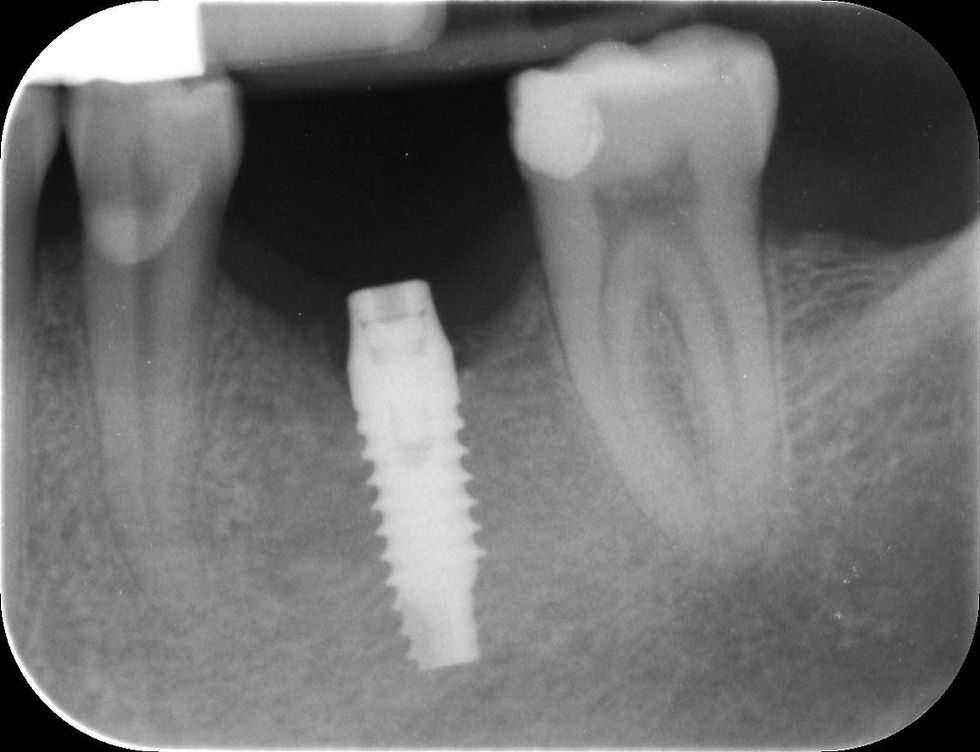

Post-surgical radiograph.